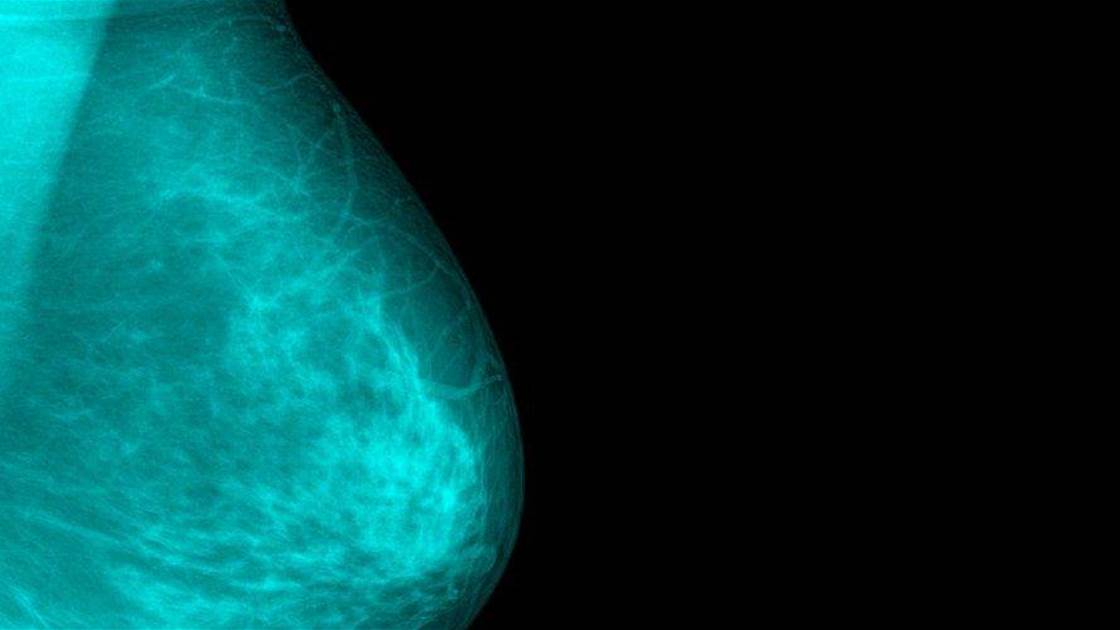

Breast cancer diagnosis often goes something like this: a woman feels a lump on her breast and makes a doctor's appointment. The doctor conducts some tests-which may include a breast exam, mammogram, ultrasound, biopsy, or a combination-and determines the lump is cancerous. That's why women are encouraged to complete self exams regularly and be familiar enough with their breasts to notice any changes.

But a lump isn't the only symptom of breast cancer. In fact, preliminary research suggests that 1 in 6 women diagnosed with breast cancer first report a symptom other than a lump. Because there's not as much awareness of these less common symptoms, the researchers hypothesised that so-called "atypical presentations" could be delaying some women's diagnoses. Of course, an earlier diagnosis results in earlier treatment, which typically tends to work best, says breast surgical oncologist Dr Joseph Weber.